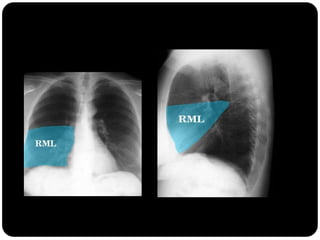

Atelectasia do Lobo Médio

Impacto mínimo

sobre volume total

do hemisfério

direito (é o menor

dos lobos) LS e LI

inferior compensam

Sinal da silhueta

Lobo médio: borra o contorno direito do coração.

1. Qual lobo está afetado? Por quê?

É atelectasia?

Lobo

médio(segmento

medial e lateral;

Borra contorno

cardíaco direito

E não é atelectasia!

A fissura horizontal

não está deslocada.